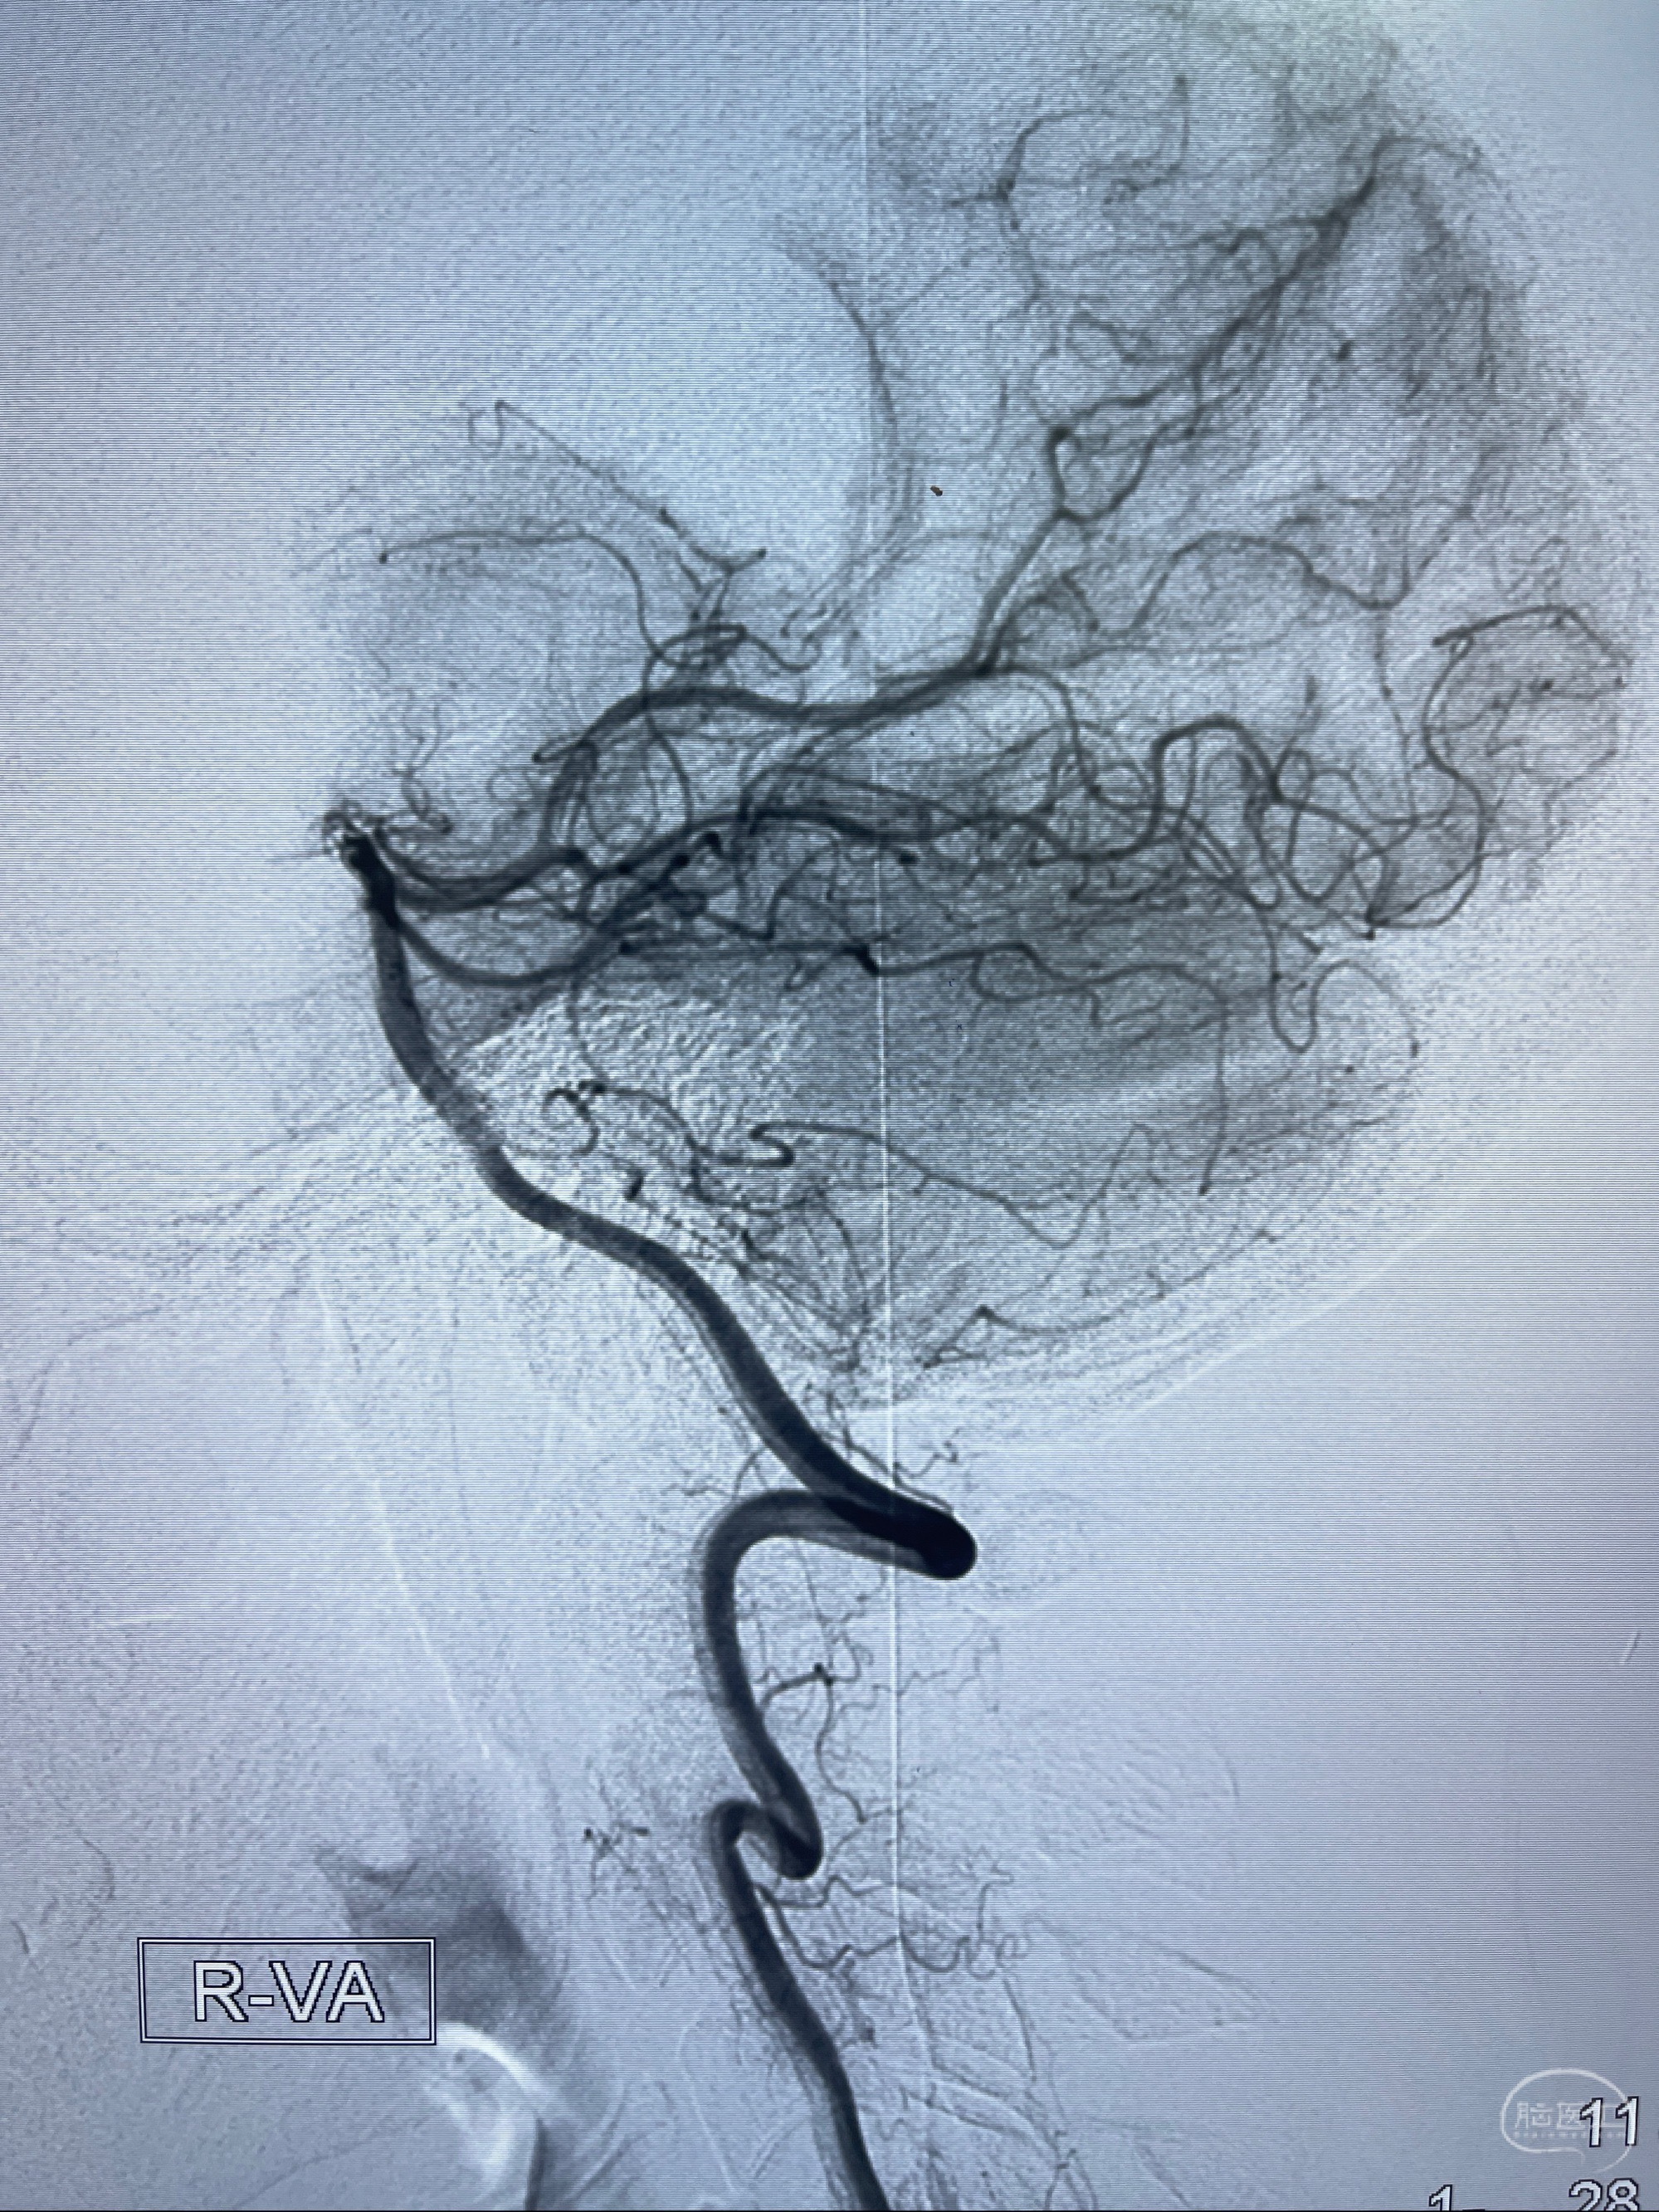

2023-07-27全脑血管造影:双侧颈内动脉眼动脉段动脉瘤,右侧较大

2023-08-01全麻下行双侧颈眼动脉瘤支架辅助栓塞